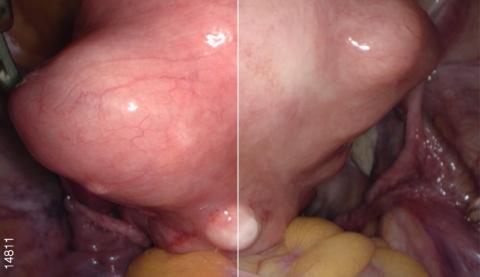

Видеоэндоскопическая система OLYMPUS VISERA 4K UHD обладает высококачественным изображением 4K и технологией узкоспектральной визуализации изображения NBI. Высокое разрешение позволяет визуализировать малейшие изменения в структуре тканей для ранней диагностики очагов воспаления и опухолей. Чем выше разрешение изображения, тем больше вероятность обнаружения очаговых изменений на ранней стадии. Процессор OTV-S400 позволяет получать изображения с разрешением 3840 х 2160 пикселей, что помогает увидеть значительно больше. Система поддерживает визуализацию в форматах 4K UHD (3840 × 2160) и Full 4K (4096 × 2160).

NBI - это оптическая технология, которая позволяет визуализировать мельчайшие структуры кровеносных сосудов и слизистой оболочки. В основе технологии лежит принцип поглощения гемоглобином волн определенного спектра (415 и 540 нм). Благодаря уникальным правилам распределения цветов, конечное изображение имеет цветопередачу отличную от обычной.

Данная технология позволяет с большей точностью визуализировать кровеносные сосуды и слизистую оболочку, а также диагностировать патологические процессы.

Расширенная цветовая гамма

Видеопроцессор OTV-S400 создает расширенную цветовую гамму за счет использования формата цвета 4K (BT2020). Это обеспечивает насыщенную цветопередачу и соответствующие цвета для каждой области. Благодаря этому происходит упрощение определения границ тканей (жира, нервов, сосудов и т. п.) и улучшенная визуализация кровеносных сосудов и пораженных участков.